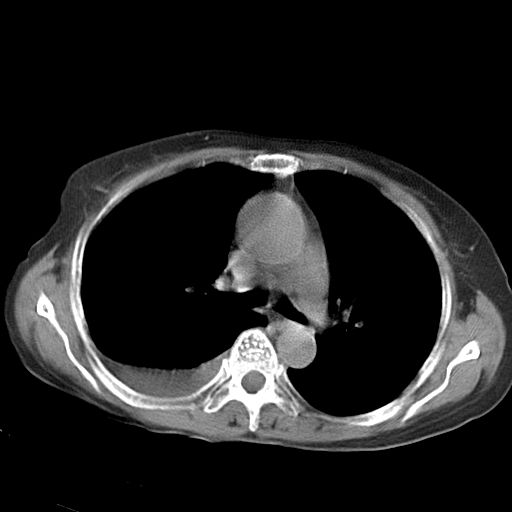

以下是引用dyqct在2006-12-7 21:08:00的发言:[br]考虑:1、肝内外胆管多发性结石伴肝左叶外侧段肝萎缩;[br] 2、右膈下多发脓肿;[br] 3、右侧少量胸腔积液、斜裂积液;[br] 4、左肾囊肿。

以下是引用拾荒者在2006-12-7 21:44:00的发言:[br]肝内外胆管多发结石,右膈下多发脓肿,右胸膜腔及叶间裂积液,左肾囊肿。[br] [br]